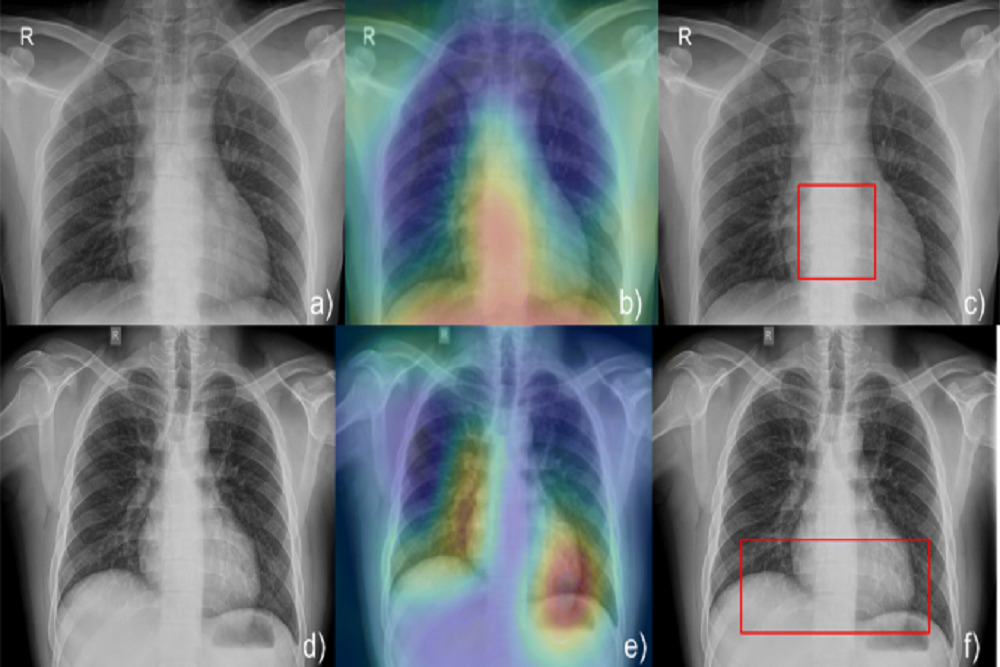

The new system features a user-assisting intelligence (AI) tool that combines patient data and observed information to find the best positioning and other parameters for each patient and exam. The AI helps technologists perform exams that deliver consistent and high-quality images for the radiologist to interpret. An additional benefit to the patients is the low dose used to capture the high-quality images.